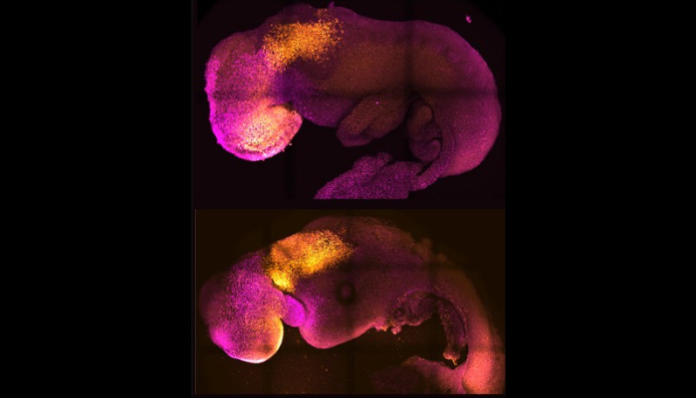

foto: Gianluca Amadei, Charlotte Handford / Nature

¿Qué lograron? Que las células madre “se autoorganizaron en estructuras que progresaron a través de las sucesivas etapas de desarrollo hasta tener corazones que latían y las bases del cerebro, así como el saco vitelino donde el embrión se desarrolla y obtiene los nutrientes en sus primeras semanas”. “A diferencia de otros embriones sintéticos, los modelos de embrión desarrollados por Cambridge alcanzaron el punto en el que todo el cerebro, incluida la parte anterior, comenzó a desarrollarse. Se trata de un punto de desarrollo más avanzado del que se ha alcanzado en cualquier otro modelo derivado de células madre”, afirma el sitio.